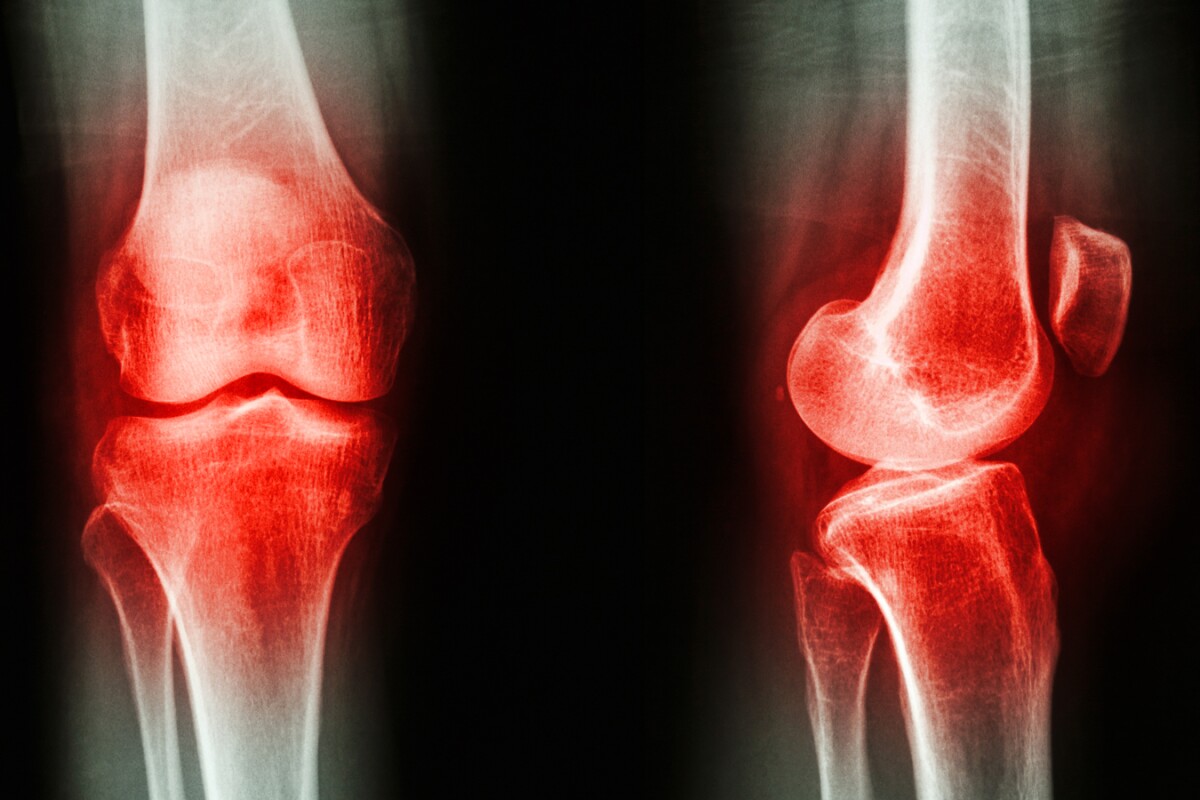

Osteoarthritis Blood Test . Two main types of lab tests are used in diagnosing osteoarthritis. Learn how these tests are performed and what they show doctors. There are no blood tests that can diagnose oa; There is no blood test for osteoarthritis, but blood tests can rule out other diseases that cause secondary osteoarthritis. Taking joint fluid samples to look for other causes of joint pain, such as. No, but sometimes a healthcare provider will perform certain blood tests in order to rule out oa. Is there a blood test for osteoarthritis? Having blood tests to rule out other causes for symptoms. Most such tests are used to differentiate. Risk factors include genetics, female sex, past trauma,. Osteoarthritis is the most common type of arthritis (a condition that affects your joints). Osteoarthritis is a common degenerative disorder of the articular cartilage associated with hypertrophic bone changes. Doctors test blood, enzymes and other fluids and perform skin or muscle biopsies to help them diagnose and monitor arthritis. However, your doctor may order them to rule out other causes. Although there's no blood test for osteoarthritis, certain tests can help rule out other causes of joint pain, such as.

Two main types of lab tests are used in diagnosing osteoarthritis. Taking joint fluid samples to look for other causes of joint pain, such as. Most such tests are used to differentiate. Is there a blood test for osteoarthritis? Osteoarthritis is a common degenerative disorder of the articular cartilage associated with hypertrophic bone changes. There is no blood test for osteoarthritis, but blood tests can rule out other diseases that cause secondary osteoarthritis. Although there's no blood test for osteoarthritis, certain tests can help rule out other causes of joint pain, such as. Osteoarthritis is the most common type of arthritis (a condition that affects your joints). Risk factors include genetics, female sex, past trauma,. Doctors test blood, enzymes and other fluids and perform skin or muscle biopsies to help them diagnose and monitor arthritis.

Osteoarthritis Blood Test Two main types of lab tests are used in diagnosing osteoarthritis. Although there's no blood test for osteoarthritis, certain tests can help rule out other causes of joint pain, such as. However, your doctor may order them to rule out other causes. There is no blood test for osteoarthritis, but blood tests can rule out other diseases that cause secondary osteoarthritis. Osteoarthritis is a common degenerative disorder of the articular cartilage associated with hypertrophic bone changes. No, but sometimes a healthcare provider will perform certain blood tests in order to rule out oa. Is there a blood test for osteoarthritis? Most such tests are used to differentiate. Taking joint fluid samples to look for other causes of joint pain, such as. Having blood tests to rule out other causes for symptoms. Osteoarthritis is the most common type of arthritis (a condition that affects your joints). Risk factors include genetics, female sex, past trauma,. Two main types of lab tests are used in diagnosing osteoarthritis. Learn how these tests are performed and what they show doctors. Doctors test blood, enzymes and other fluids and perform skin or muscle biopsies to help them diagnose and monitor arthritis. There are no blood tests that can diagnose oa;